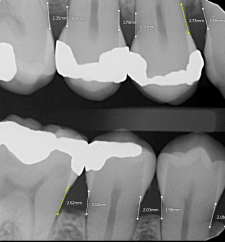

Caries Detection

The best for last and arguably the most well-thought-out feature. Especially with the tooth segmentation mode, which makes it easier for patients to understand their diagnosis and treatment plans.

The system uses two shades of pink to indicate potential caries:

- Light pink: Incipient caries (100% in enamel) - we will often review

- Darker magenta: Caries extending into dentin - we need to restore

The system even provides a percentage breakdown of enamel vs. dentin involvement. I have been blown away by its accuracy while using it, and it makes something that feels quite subjective (reading shades of grey) into a science.

This feature is very useful for patient education and deciding between preventive measures and restorative treatment. However, remember that radiographic evidence alone is not always sufficient for a definitive caries diagnosis.

“ToothParts” in Presentations

The ability to toggle the ToothParts feature during case presentations is one of the most powerful patient education tools I have seen.

Visually distinguishing different tooth structures helps patients better understand their conditions and proposed treatments.

In combination with caries and bone loss AI diagnosis, it really works incredibly well and what I appreciate the most about Pearl is that it seems to be designed with presenting to the patient in mind. As its so simple for someone who is non-dental to understand and follow along.